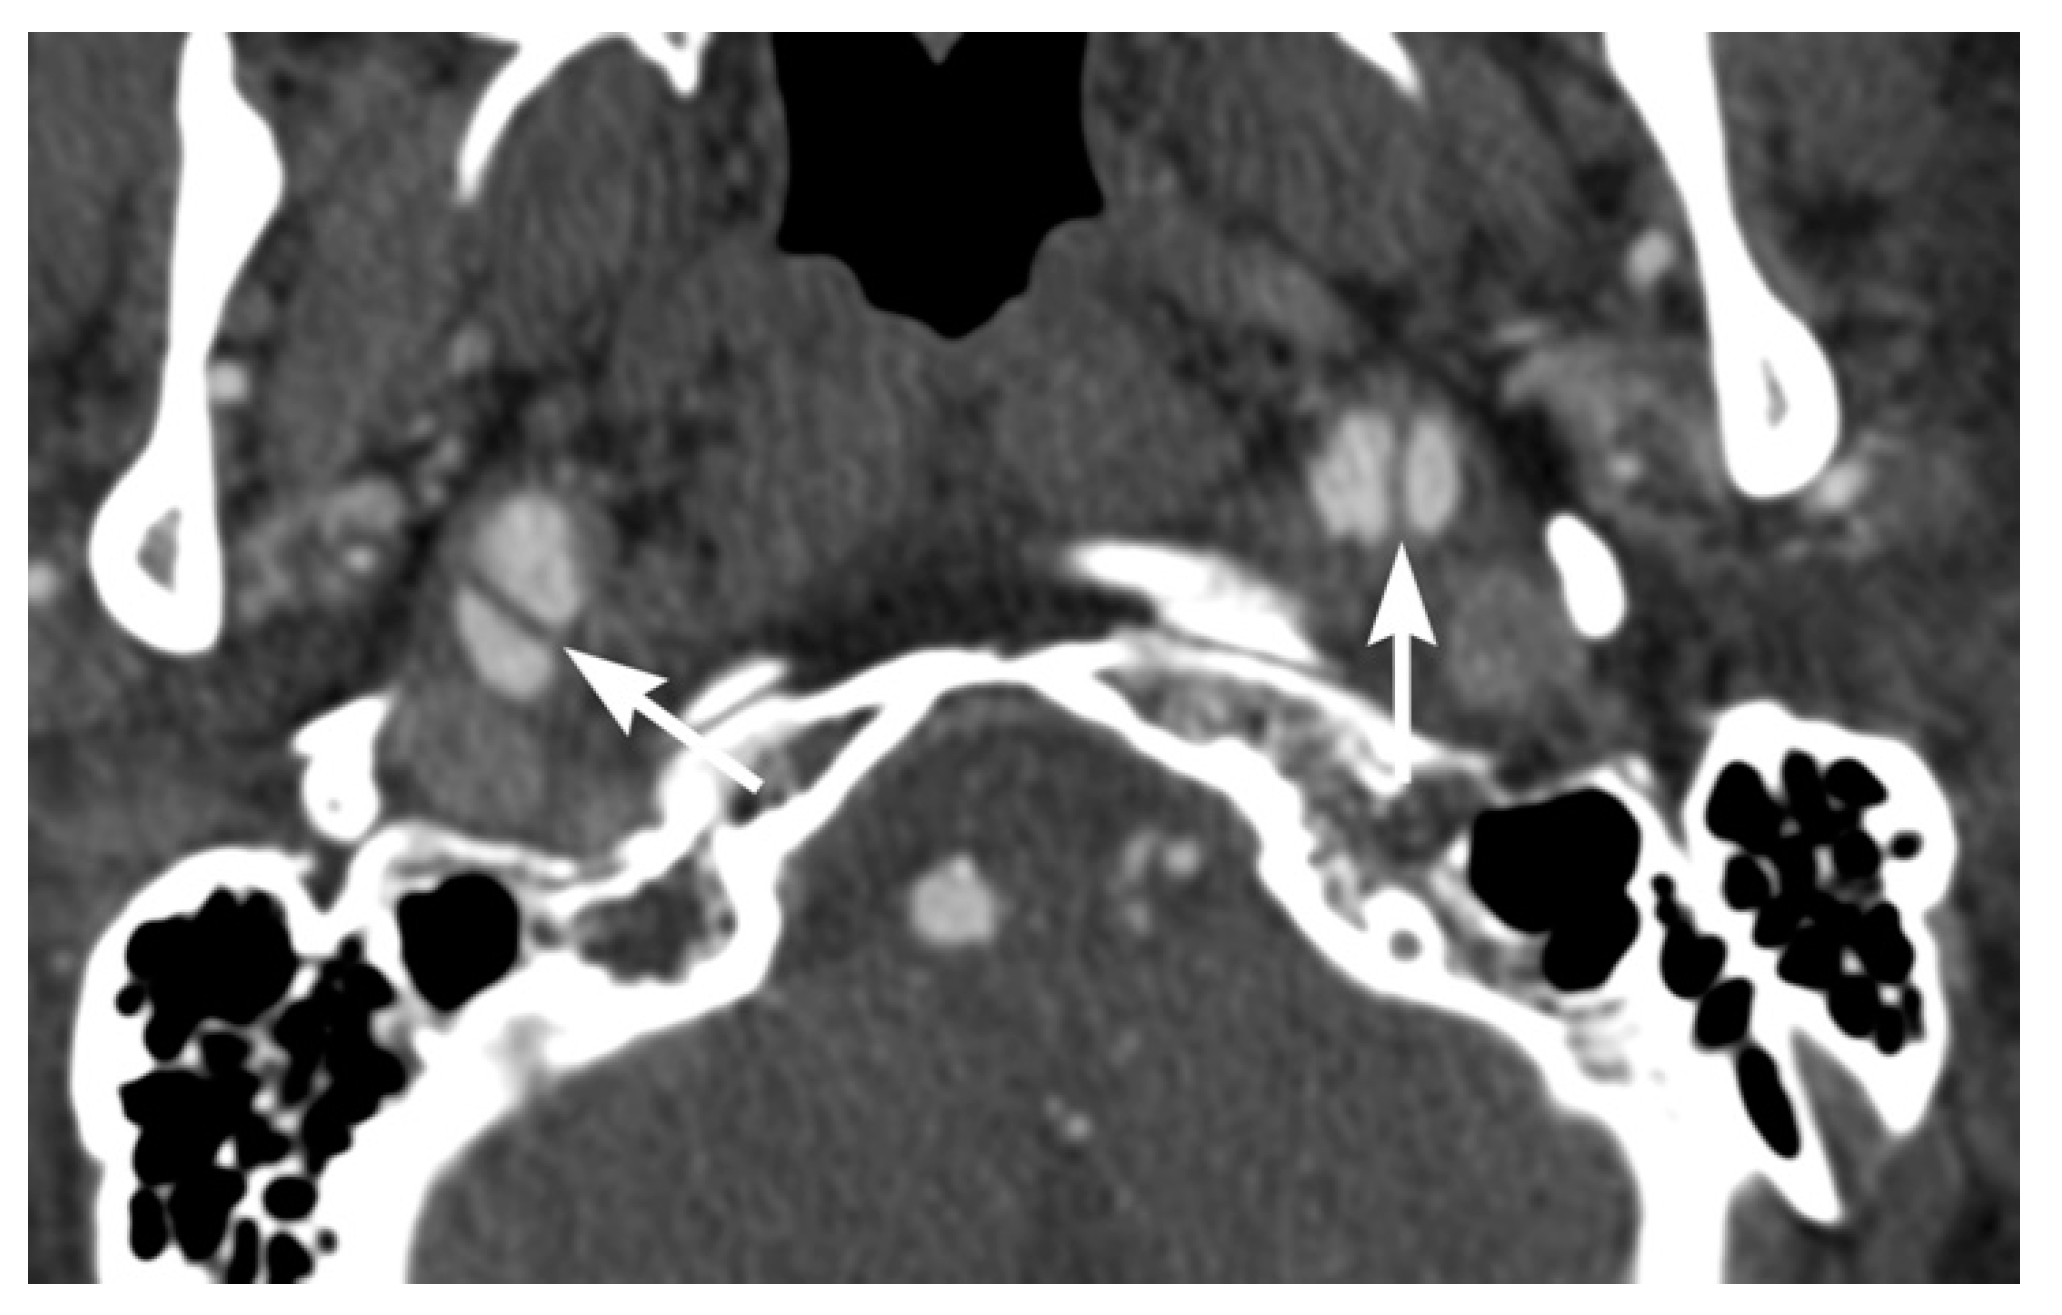

3. Imaging Findings of Arterial Injury